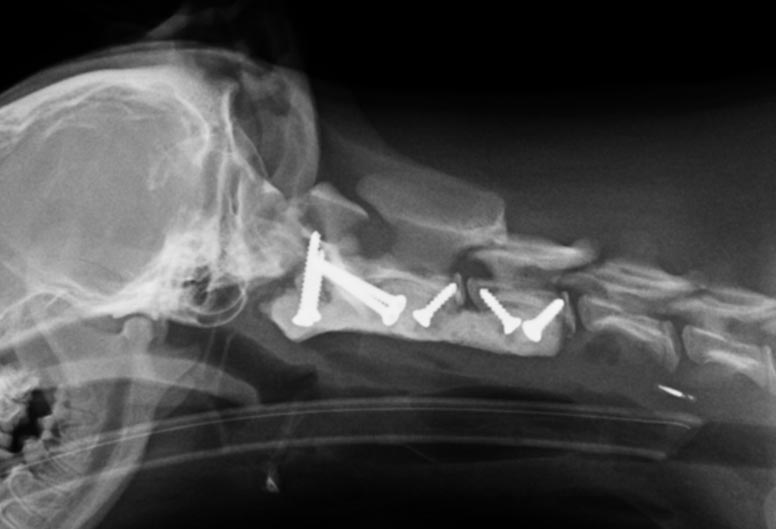

Patricia arranged for cervical radiography to help make a diagnosis and discovered that Ella’s cervical vertebrae had not developed so the alignment of her spine wasn’t correct. As she gently moved her neck the C1-C2 joint were trapping her spinal cord, causing her to collapse. She had a malformed C2 vertebra (missing odontoid process) and also had a curvature of the spine at C2-C3 possibly resulting from missing or weakened ligaments. She had been born with a wonky spine that was damaging her spinal cord as she was moving around.

It was agreed that surgery would be needed to stabilise Ella’s vertebrae and stop any further damage. This would involve implants to replace the missing or weakened ligaments.

Felipe de Vicente, Specialist in Small Animal Surgery, was called upon to help with the surgery, using a CT scan of Ella’s spine to plan where the implants were needed.